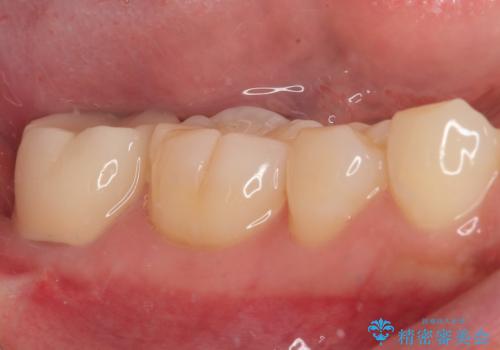

後方は歯肉内にまで虫歯が及んでいたため、歯肉の一部を切除して、クラウンとの境目を明示して処置を行いました。

クラウン装着後には、来院時に気になさっていた歯肉の腫れが解決され、快適に生活を送れるようになりました。